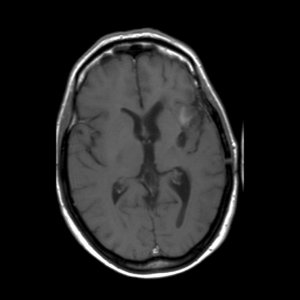

Een astrocytoom graad III groeit onbehandeld snel door in het omliggende hersenweefsel; de ziektegeschiedenis is daarom meestal relatief kort. De meeste patiënten zijn tussen de 30 en 50 jaar oud, iets vaker mannen dan vrouwen. Een MRI toont meestal een grillige, slecht begrensde tumor die met contrast kan aankleuren. De diagnose moet gesteld worden door onderzoek van het weefsel.

'Hoe is het mogelijk, dit kan niet, dit is bizar, zoiets heb ik nog nooit gezien maar het is waar'. Dit waren de woorden van de neuro-oncoloog. Mijn vriendin Ineke en ik bogen ons naar haar computer waar het onverklaarbare resultaat stond. Op de MRI-scan was te zien dat de kwaadaardige tumor zich had teruggetrokken. De tumor had een donkere holte met een grillige tumorrand achtergelaten. De neuro-oncoloog benadrukte nog eens dat het echt heel bijzonder was en dat zij en de radioloog voor een raadsel stonden. Ik vroeg haar wat dit betekende voor de prognose van mijn levensverwachting. Ze zei dat er nog één of misschien zelfs twee jaar zou bijkomen. Meer durfde ze er ook niet over te zeggen.

De MRI-scan van oktober 2009

De MRI scans van 2006 en 2007 zijn niet correct geïnterpreteerd. Wat toen als tumorgroei werd gezien blijkt nu een reactie van de bestraling te zijn. De chemokuur was overbodig omdat de tumor niet groeide. Wat je nu ziet is de tumor die enigzins gegroeid lijkt, maar dat is niet zeker. Als het zeker is moet je overwegen om opnieuw bestraald te worden. Meer patienten zijn ook met de verkeerde boodschap (dat de tumor groeit) naar huis gegaan,ook in andere ziekenhuizen.